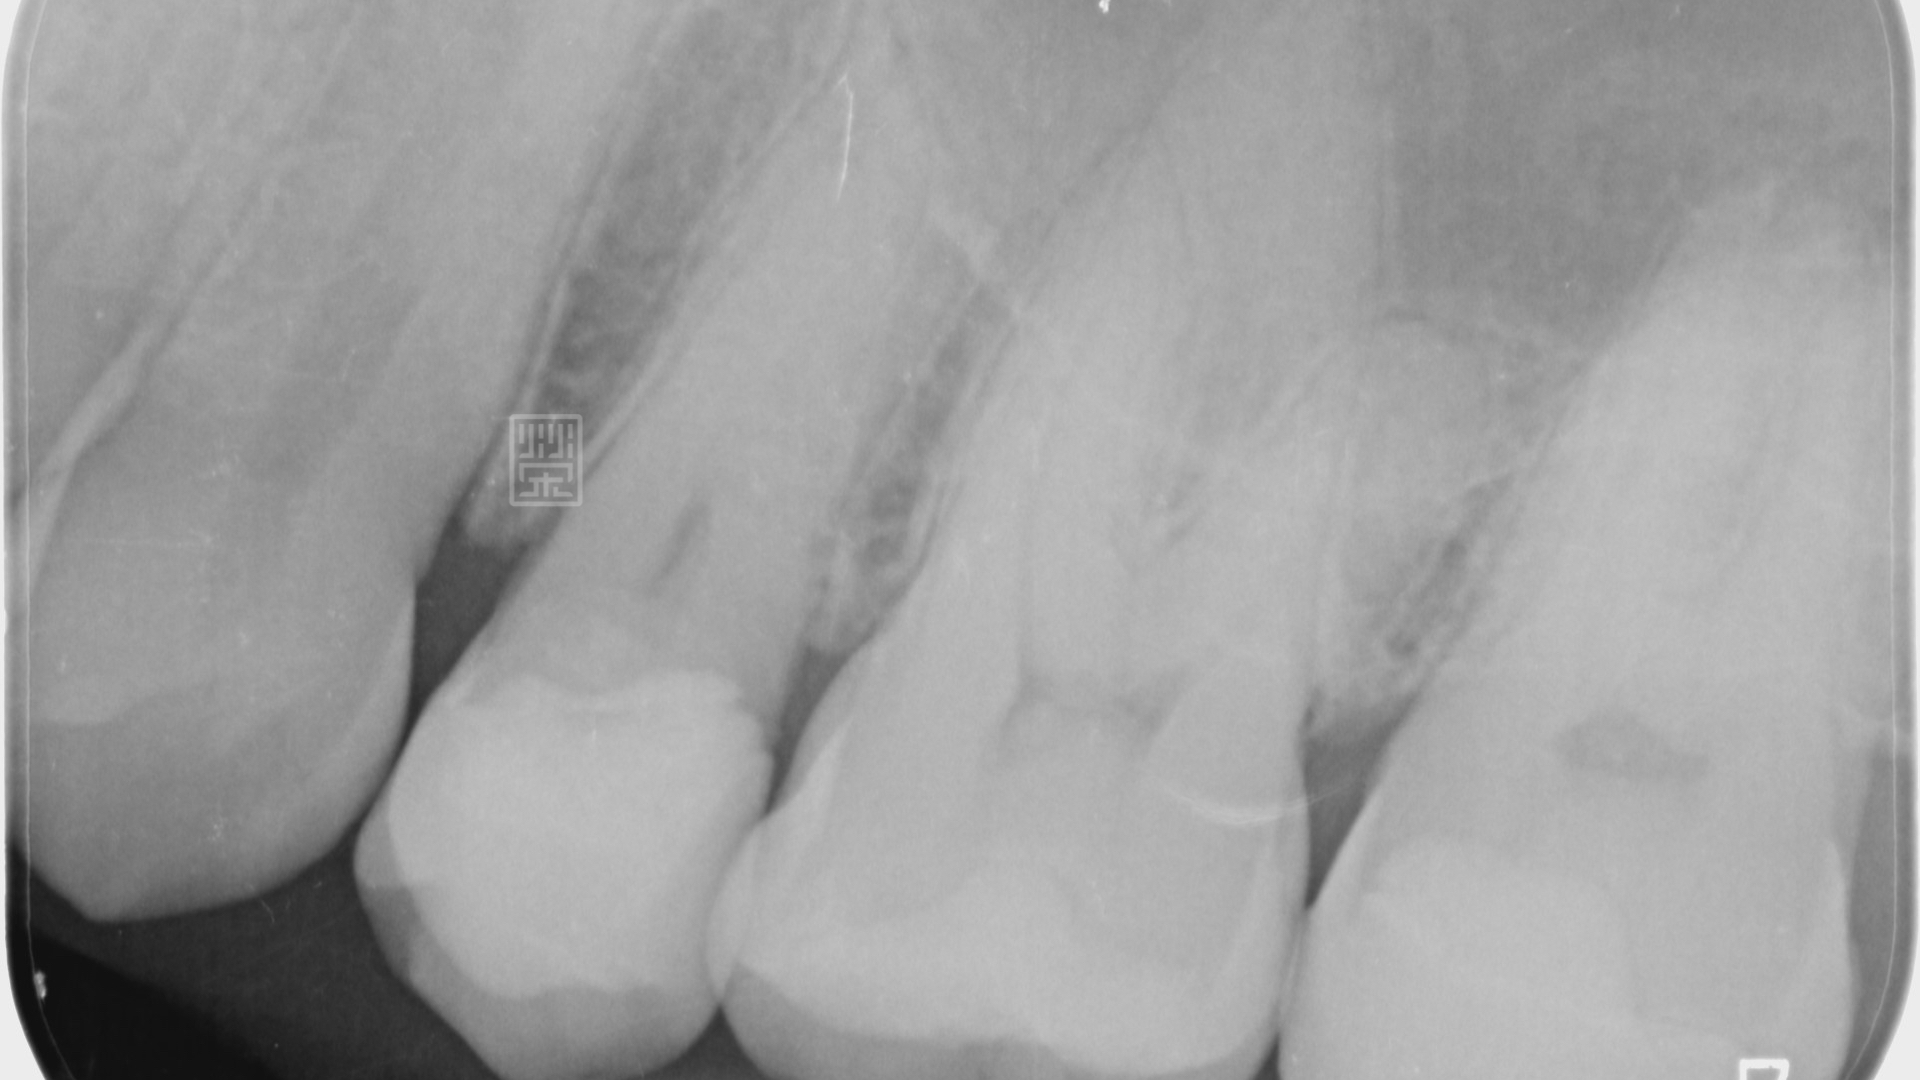

X光檢查下,雖然咬合面的蛀洞小,但是下方有很嚴重的蛀牙

將舊填補物與蛀牙清除後,剩下兩片薄薄的齒質,看上去就像是卡通蘋果被咬一圈,首先先考量牙髓神經的健康性,X光與臨床檢查上,牙髓仍是健康的狀態,但是剩餘健康的齒質這麼少,要怎麼恢復牙齒的強度呢?

利用黏著式嵌體對牙齒只需做最少的修磨,但是在頰側,為了有好的外觀,所以包覆到牙齦邊緣,空間厚度以最小厚度0.3毫米為製作空間,減少對牙齒的傷害,完成全瓷嵌體後,恢復理想的功能與美觀,也利用全瓷嵌體的特性,保存了牙齒,減少牙齒需要拔牙的可能性。